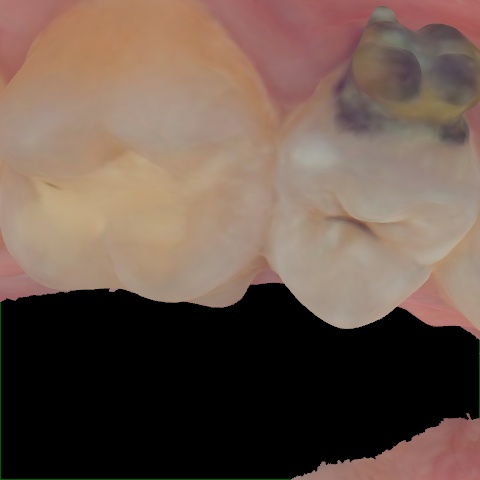

Image 735 / 1535

NHD39990

Annotated as "Good"

Original Image Rendering Image